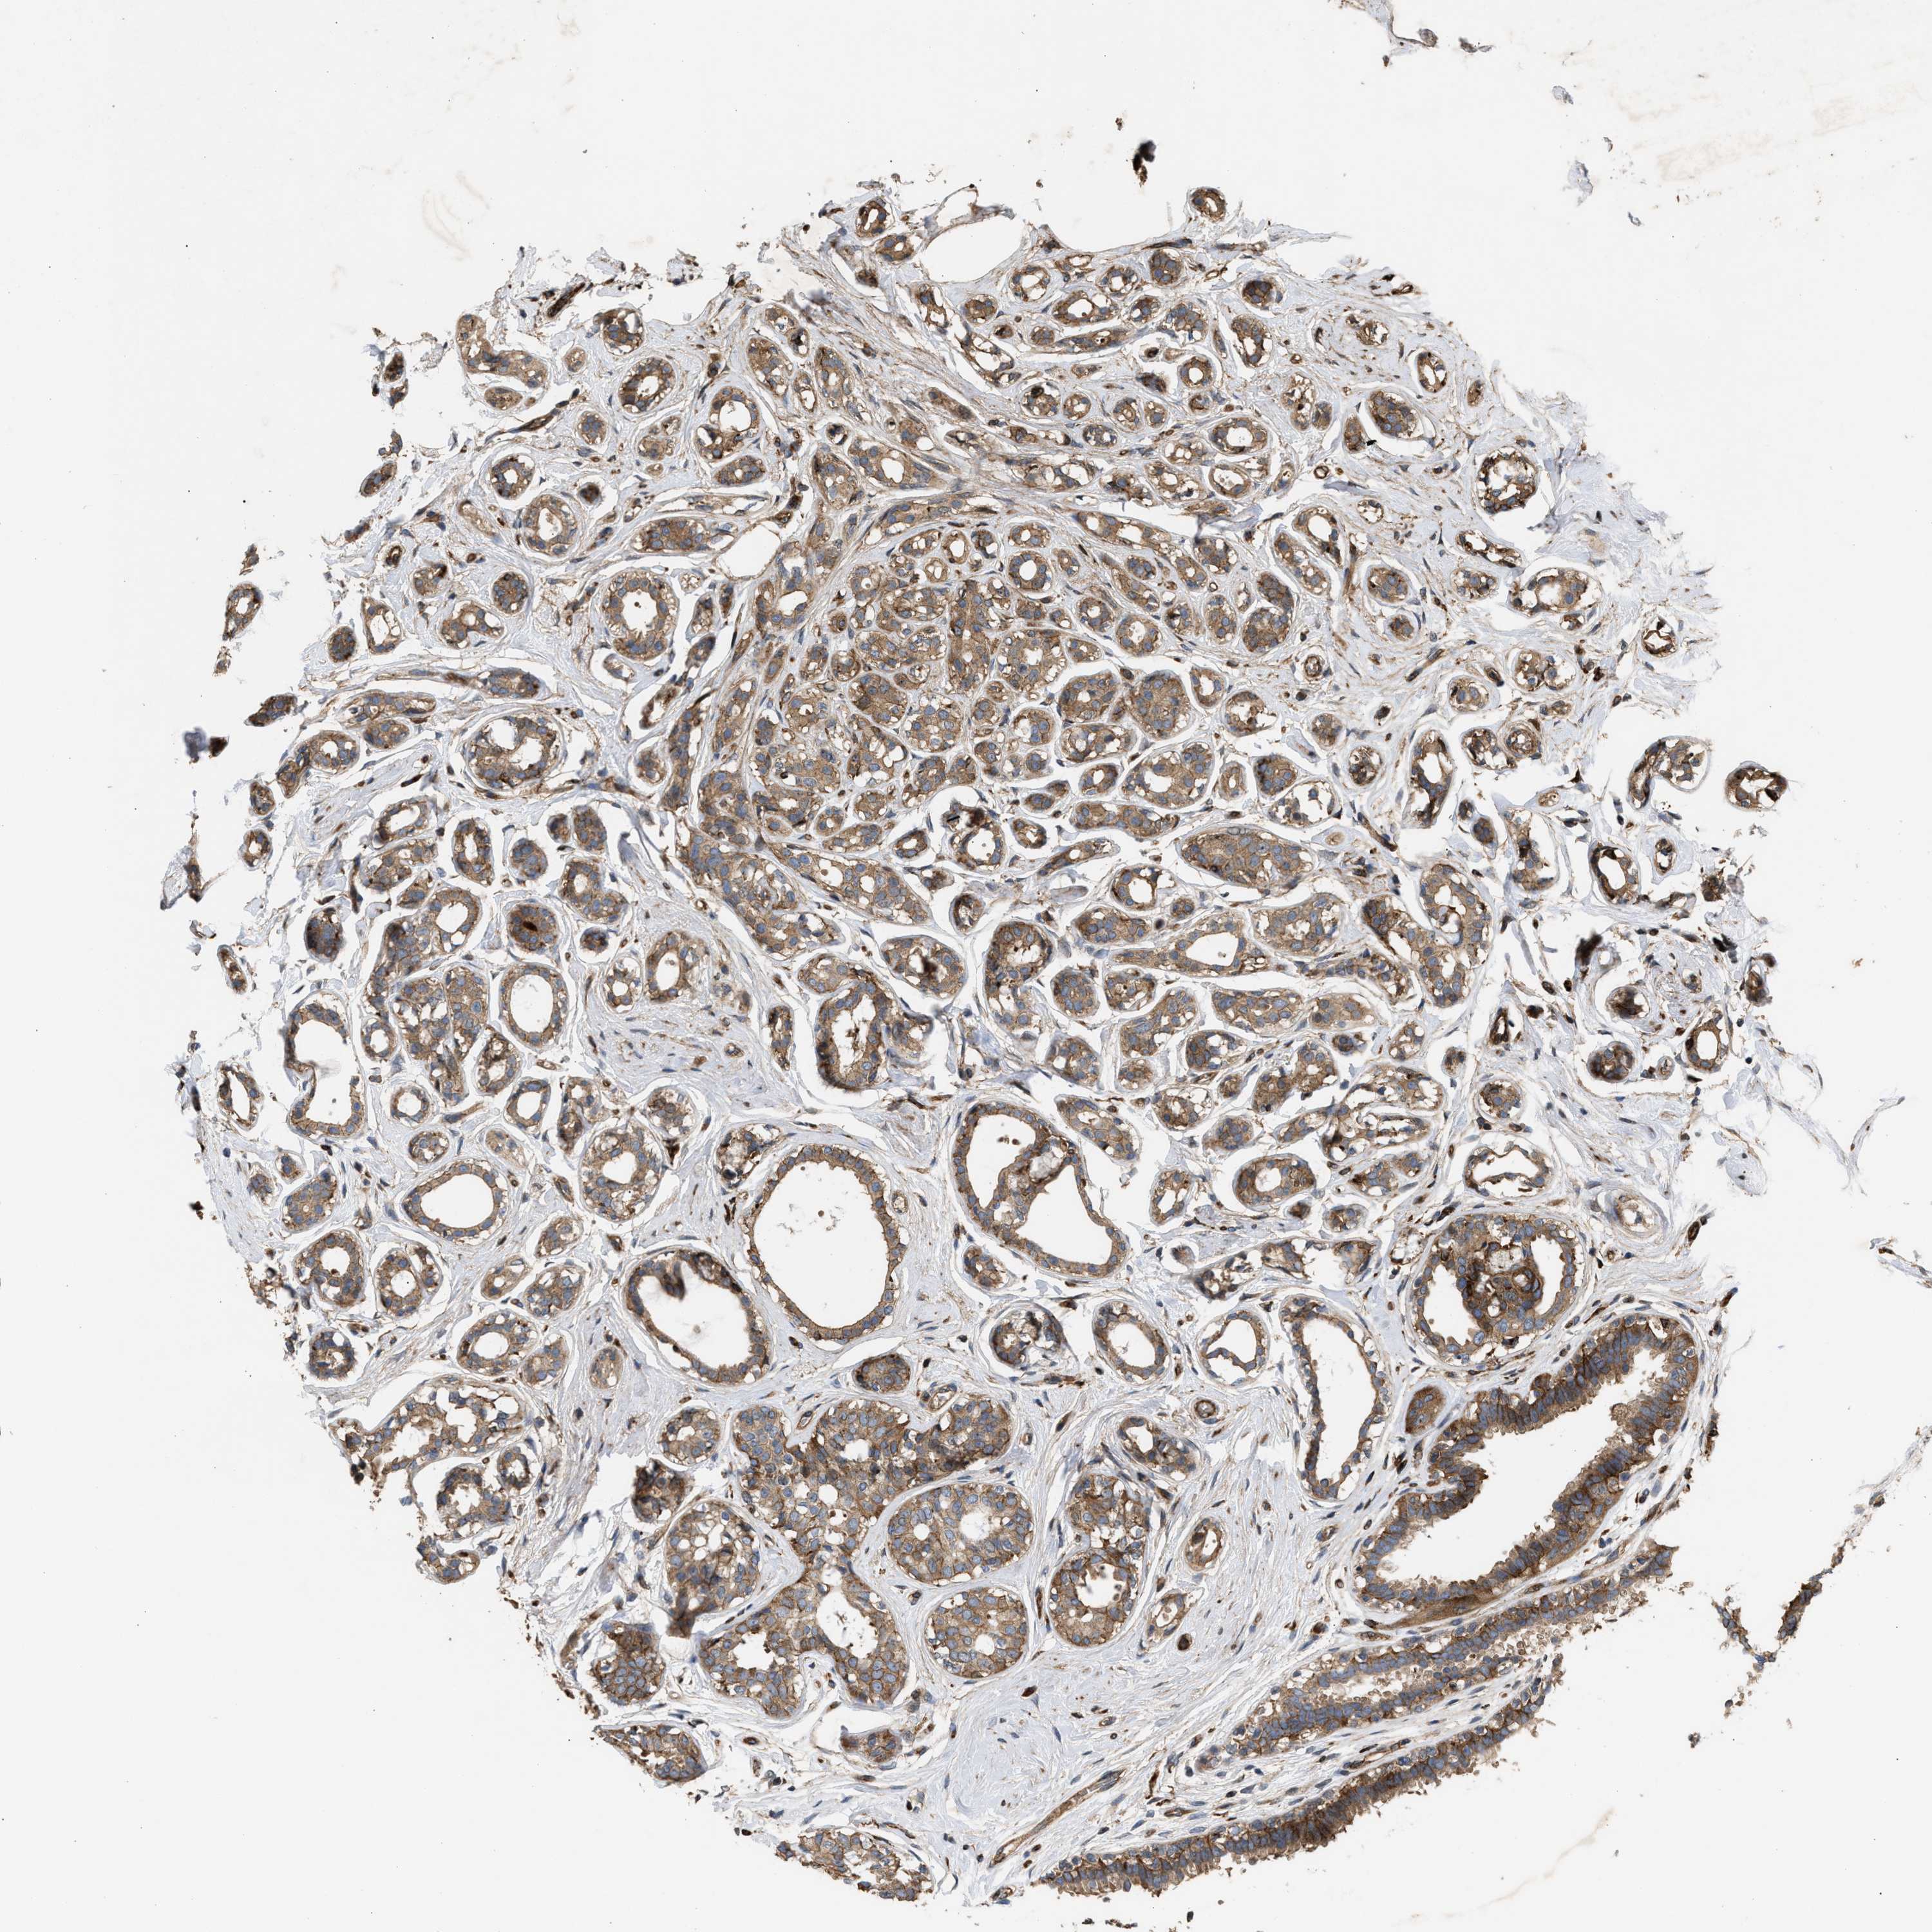

CANCER BREAST CANCER Show tissue menu

BRCA TCGA BRCA VALIDATION PROTEIN EXPRESSION